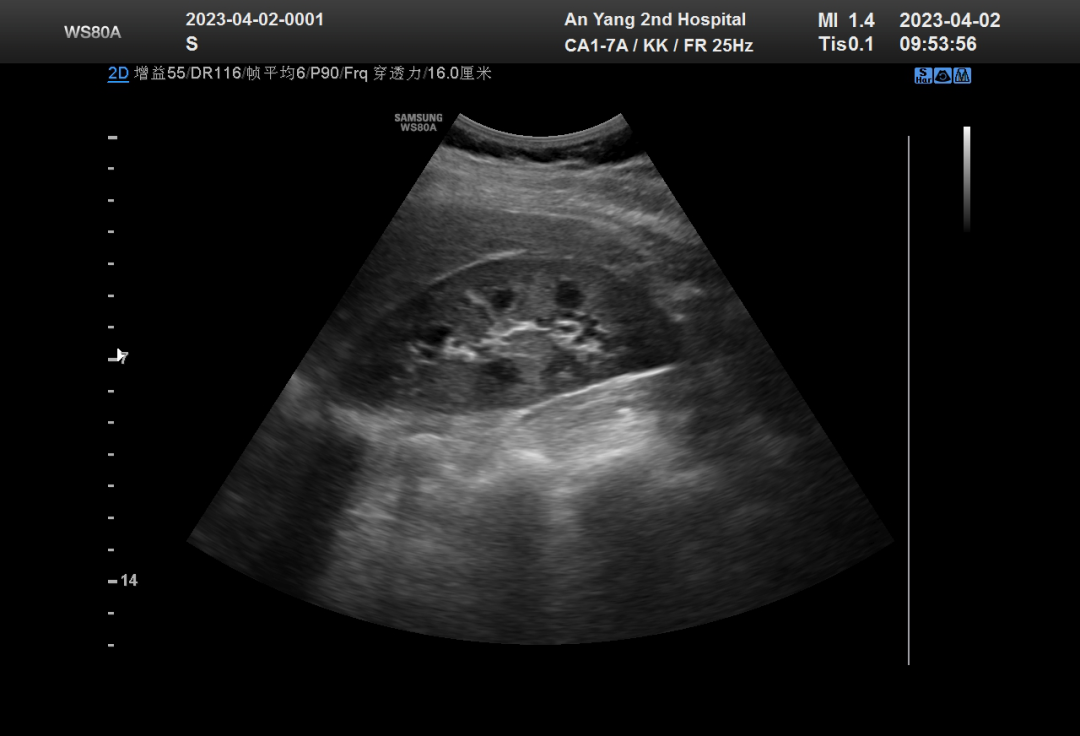

二維超聲又稱(chēng)B型超聲。超聲成像是利用探頭發(fā)射超聲波,超聲聲速掃描人體,因組織聲阻抗的不同產(chǎn)生反射超聲波,聲速傳播途徑中遇到的各個(gè)界面產(chǎn)生的一系列反射和散射信號經(jīng)過(guò)處理后顯示為不同的圖像,它屬于黑白成像。